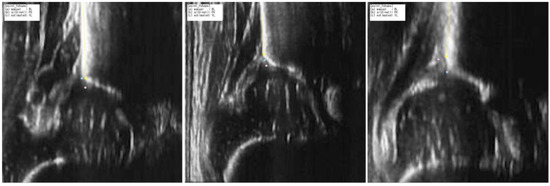

2.3.2. Quality Assessment Through Signal Heterogeneity Analysis